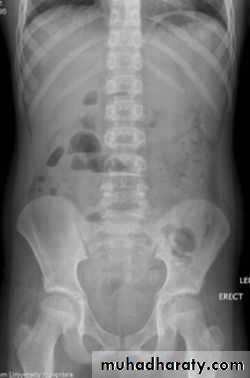

• Supine AP• Erect AP

The main purpose of horizontal beam films is to detect air-fluid levels and free intraperitoneal air

Dilatation of the bowel

Dilatation of the bowel is the cardinal plain film sign of intestinal obstruction

If the bowel is dilated it is important to try and decide which portion is involved

Causes of bowel dilatation

• Mechanical SB obstruction : small bowel dilation with normal or reduced caliber of colon• Mechanical LB obstruction: dilated colon down to the point of obstruction. May be accompanied by small bowel dilation if the ileocecal valve becomes incompetent

• Generalized paralytic ileus: SB and LB dilatation, gas may be present in the rectum